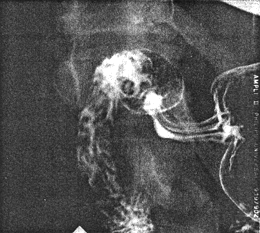

In radiological and experimental anatomical studies of mucosal fold movements Keet (l974, l978) found that normally, transverse or oblique mucosal folds could be demonstrated in the pyloric sphincteric cylinder while the latter was distended or relaxed (Fig. 13.16). (Comment: The terms "transverse" and "oblique" indicate the direction in relation to the long axis. Folds which appear transverse on the two- dimensional radiographic image are in reality circular, surrounding the tube-like lumen. Oblique folds are of a spiral nature).

![]() |

| Fig. 13.16. Pyloric sphincteric cylinder partially distended. All its mucosal folds are transverse (i.e. circular) |

During contraction of the sphincteric cylinder the folds changed in direction, becoming progressively more longitudinal, and with maximum contraction only longitudinal folds were present in the fully contracted pyloric canal (Fig. 13.17). This was a regular occurrence in all our normal cases, including those described here, and appears to be one of the best examples of co-ordinated movements between the muscularis externa and mucosa (muscularis mucosae) occurring in the gastro-intestinal tract.

| Fig. 13.17. Sphincteric cylinder contracted (arrows). The folds have changed in direction to become longitudinal. RPL, right pyloric loop; LPL, left pyloric loop. Note pseudodiverticulum between loops |